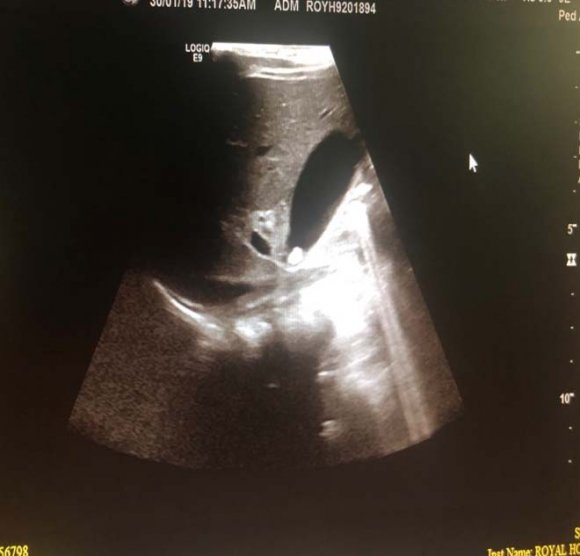

? Dedifferentiated liposarcoma ? Myxoid liposarcoma ? Pleomorphic liposarcoma ? Myxoid pleomorphic liposarcomaIn atypical lipomatous tumour/well differentiated liposarcoma adipocytic variant consists out of cells that vary substantially in size as well as cells that have Dedifferentiated liposarcoma can arise as a synchronous lesion in 90% of cases and as metachronous lesion in 10% of cases 6 . These tumours exhibit a wide morphological spectrum and histologically show areas of high grade, poorly differentiated sarcoma resembling high-grade myxofibrosarcoma, fibrosarcoma, malignant solitary fibrous tumour or pleomorphic sarcoma not otherwise specified. Dedifferentiated liposarcomas can be of variable histological grade 5 . Dedifferentiated liposarcomas is an aggressive disease, arising most commonly in the retroperitoneum and is associated with high rates of local and metastatic recurrence and disease specific mortality 7 Use of the term atypical lipomatous tumour is determined by tumour location and resectability. In locations such as the retroperitoneum, it is usually impossible to obtain a wide tumour free surgical margin of more than 2cm, thus local recurrence is common and leads to mortality, seen in the absence of dedifferentiation or metastases The introduction of computed tomography (CT), magnetic resonance imaging (MRI), and ultrasonography have greatly enhanced our capability to make the diagnosis of abdominopelvic neoplasms and determine and direct treatment, as well as observe the progress of the neoplasm and effect of treatment over time. Identification of a retroperitoneal mass at imaging is a challenging task for radiologists, however the presence of fat within a retroperitoneal lesion is helpful in refining the differential diagnosis 9 ? On ultrasound appearance it is hyperechoic and may demonstrate posterior acoustic shadowing . It is easy to recognize fat within a lesion due to its characteristic imaging appearance: